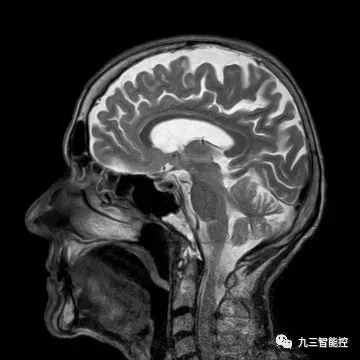

原始图像

(5)大脑核磁共振图像(侧面)